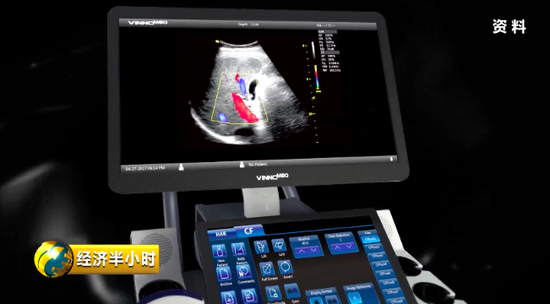

“彩超”,人们并不陌生,但是既能诊断又能帮助治疗的“彩超”对大多数人来说却是陌生的。

有一个特殊的彩色B超设备,不仅能够精确诊断,还能帮助大夫有效地给予患者治疗。也就是说,在治疗疾病时,在超声波的介入下,药物被精准送达病变位置,释放药物,从而实现靶向治疗。而且这个彩色B超设备副作用很少,安全性特别好。《经济半小时》记者在苏州工业园区了解到,目前这种彩色B超设备在国际上已经达到一流水平。

2014年,公司靠着自主创新,终于研制出具有完全知识产权、性能达到世界一流水平的彩色B超设备。

彩色B超设备